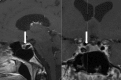

Case presentation: A 47-year-old male suffered from primary chronic cluster headache (CCH, ICHD-3 beta criteria fulfilled) since the age of 35 years. A magnetic resonance imaging (MRI) study of the brain in 2006 came back normal. He tried several prophylactic treatments but was never longer than 1 month without attacks. He was under chronic treatment with verapamil with only a limited effect on the attack frequency. Subcutaneous sumatriptan 6 mg injections were very effective in aborting attacks. By February 2014 the patient developed a continuous interictal pain ipsilateral to the right-sided cluster headache attacks. An indomethacin test (up to 225 mg/day orally) was negative. Because of the change in headache pattern we performed a new brain MRI, which showed a cystic structure in the pituitary gland. The differential diagnosis was between a Rathke cleft cyst and a cystic adenoma. Pituitary function tests showed an elevated serum prolactin level. A dopamine agonist (cabergoline) was started and the headache subsided completely. Potential pathophysiological mechanisms of pituitary tumor-associated headache are discussed.